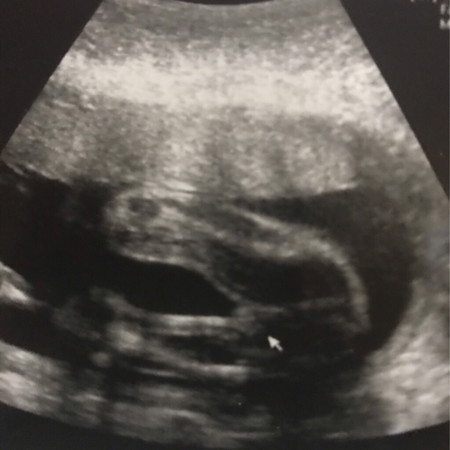

ผู้หญิงหรือผู้ชายค่ะ แม่ๆช่วยดูหน่อยค่ะ

หมอบอกผู้หญิง แต่แอบกังวลนิสๆกลัวเป็นผู้ชาย ??

ผู้หญิงรึเปล่าคะ

หญิงจ้า

คลอดแล้ว